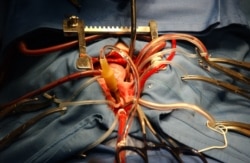

Кардиохирурги из Японии смогли "подлатать" сердце клетками из пробирки. Кардиохирурги из Японии впервые в мире провели пересадку искусственно выращенных клеток сердечной мышцы пациенту с тяжелой ишемической кардиомиопатией.

При тяжелой ишемической кардиомиопатии сердце теряет свою эластичность и мышечная ткань перестает полноценно функционировать. В тяжелых случаях при данной патологии показана пересадка сердца. Для получения искусственных "сердечных" клеток (кардиомиоцитов) авторы проекта использовали плюрипотентные стволовые клетки – взрослые клетки человека, которые перепрограммируются в эмбриональное (незрелое) состояние. Они могут делиться и превращаться в клетки других типов. Теоретически из них можно получить практически любой орган.

Далее клетки сердечной мышцы на специальных биоразлагаемых листах трансплантировали на поврежденные участки сердца. Ожидается, что именно эти новые клетки из лабораторной пробирки будут способствовать восстановлению сосудов сердца и помогут возобновить работу органа.

Сейчас врачи продолжают наблюдать за состоянием пациента и планируют провести еще девять аналогичных операций. Ученые верят, что в ближайшем будущем новая технология станет хорошей альтернативой пересадке сердца и поможет спасти не одну жизнь.